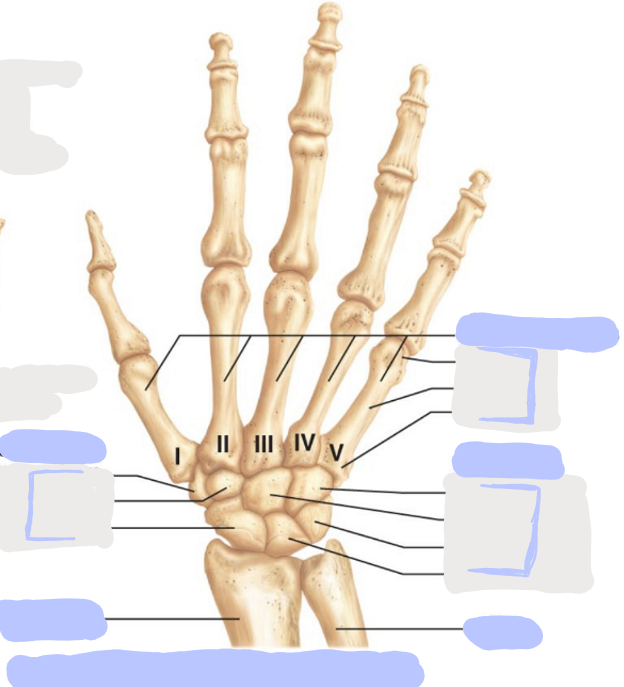

What is this picture of?

Posterior View of the Right Hand

What is here?

Where is the Ulna?

What is here?

Where is the Radius?

What is here?

Where are the Metacarpals?

What is here?

Where are some of the Carpals?

What is here?

Where are some of the Carpals?

How many carpals are there?

8

How many metacarpals are there?

5

How many phalanges are there?

14